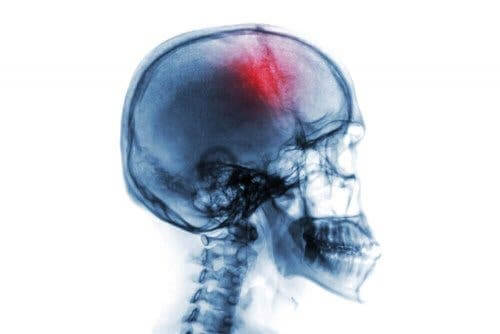

Et slagtilfælde er et brat neurologisk syndrom, som kommer med mange risikofaktorer og symptomer. Det involverer enten en blødning eller tab af blodgennemstrømning i hjernen.

Når blodtilførslen ikke når hjernen ordentligt, vil hjernevæv begynde at dø. Dermed, resulterer det i en neurologisk mangel, som kan føre til handicap eller endda døden.

I virkeligheden, refererer et slagtilfælde enten til en blødning eller forstyrrelse af blodet i et organ. Der er mange typer af slagtilfælde afhængig af det organ, der er påvirket. I et hvert tilfælde, refererer anvendelsen af ordet i sig selv som regel til et tilfælde i hjernen.